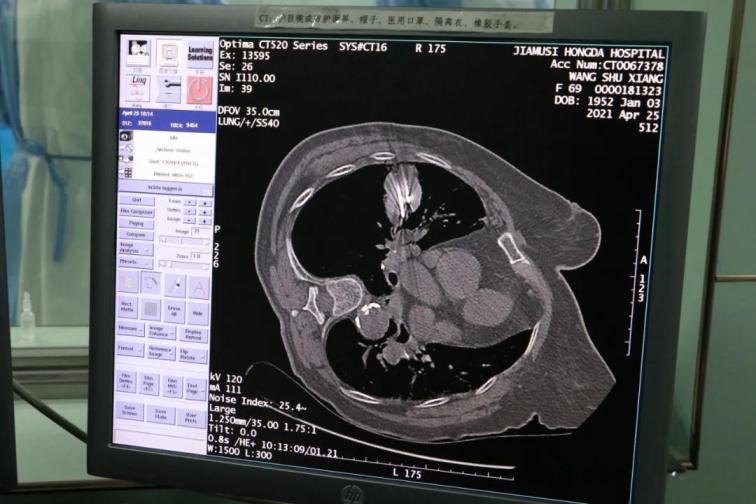

2021年4月25日,一位老年患者因肺占位在佳木斯大學(xué)宏大醫(yī)院住院治療,經(jīng)過(guò)住院后全面檢查后診斷肺小細(xì)胞肺癌,伴有心臟功能和肺臟功能不全,不能耐受手術(shù)治療和放化療治療。病人和家屬非常焦慮,多次找到我院院長(zhǎng)助理、胸外科主任周鋼教授,詢問(wèn)病情和治療方案。

為了提高CT影像下肺腫瘤定位的精準(zhǔn)度,術(shù)前胸外科團(tuán)隊(duì)聯(lián)合CT影像科趙文禮主任和董明鑫醫(yī)師詳細(xì)研究了肺CT定位方案,采取國(guó)際上先進(jìn)的CT網(wǎng)格定位法,對(duì)肺腫瘤精確定位,定位精度可達(dá)5mm以內(nèi)。經(jīng)過(guò)團(tuán)隊(duì)合作充分準(zhǔn)備后對(duì)肺癌實(shí)施了氬氦刀穿刺治療,微創(chuàng)穿刺針孔3mm,局麻鎮(zhèn)痛,分段治療40分鐘。病人全程在韋文康護(hù)士長(zhǎng)護(hù)理團(tuán)隊(duì)心肺監(jiān)測(cè)下進(jìn)行,確保了手術(shù)安全。

氬氦刀治療后即刻CT評(píng)價(jià)肺腫瘤核心密度下降,手術(shù)后5天CT評(píng)價(jià)肺癌與周圍正常肺組織對(duì)比,水腫帶形成,癌組織出現(xiàn)壞死。治療取得了良好效果。遠(yuǎn)期效果需要繼續(xù)隨訪觀察。病人手術(shù)后1周無(wú)并發(fā)癥痊愈出院。